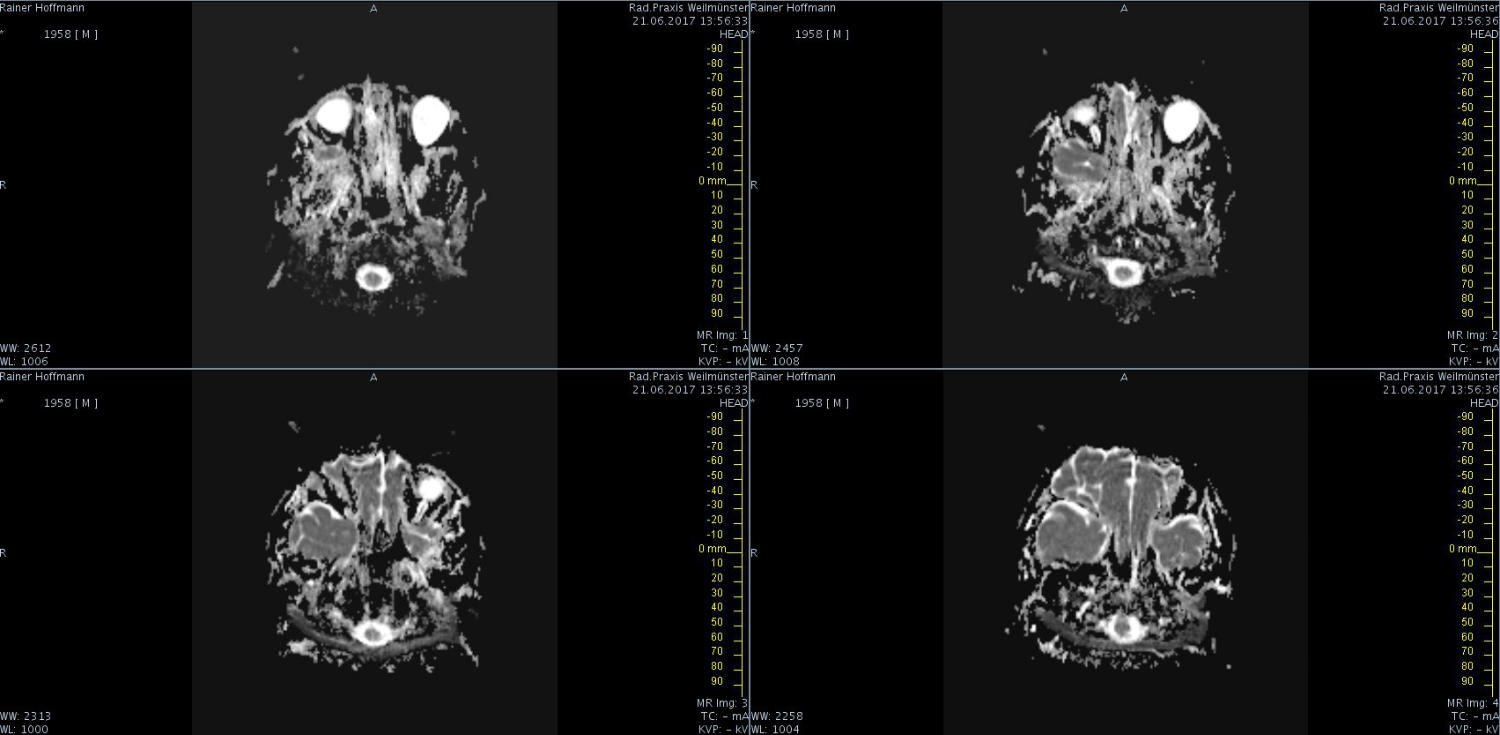

Das ist ja ganz toll, dass Ihr die Seite so schnell gefunden habt. Ich zeige euch jetzt ein ganz, ganz anderes Paßfoto von mir. Es könnte Ähnlichkeiten zu anderen lebenden oder bereits verstorbenen Personen geben. Wenn Ihr das erste Bild oben links anklickt wird es ver- größert dargestellt. Dann kann man mit den Pfeiltasten am unteren Bild- rand durch meinen Kopf blättern. Es gibt nicht viel zu sehen. Vielen Dank an Martina für Ihre Hilfe.

MRT